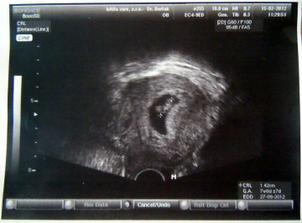

31.1. potvrzeno těhotenství 🙂 Na ultrazvuku zatím jen bublinka...

15.2. návštěva dr. kvůli špinění, naštěstí miminko v pořádku, máme srdíčko - miminko 7+1tt, vystavena neschopenka